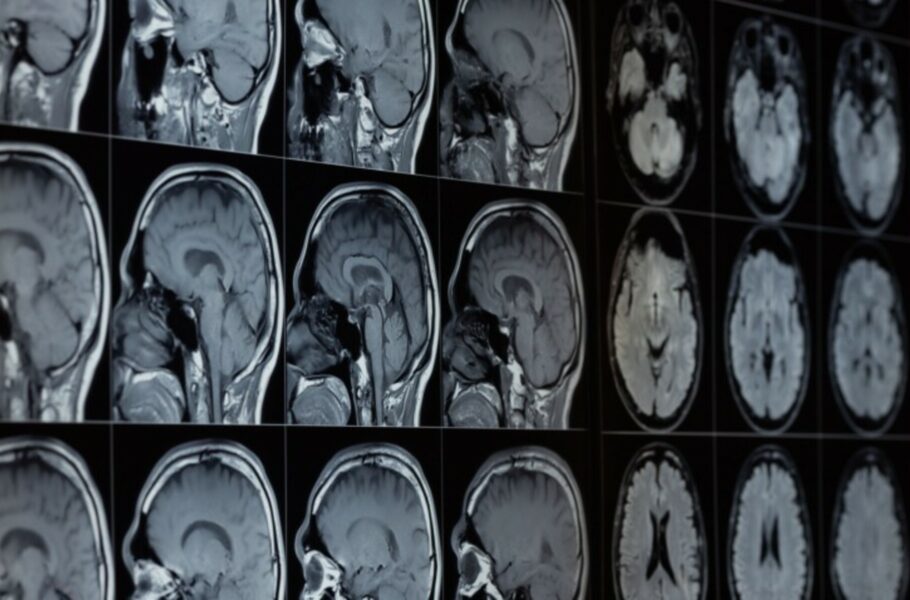

براساس اعلام رسمی مایکروسافت، ابزار هوش مصنوعی جدید این شرکت BiomedParse نام دارد. از این ابزار میتوان برای ارزیابی سیتیاسکن، امآرآی، تصاویر اشعه ایکس، اولتراسوند و انواع دیگر تصاویر پزشکی برای شناسایی مشکلات احتمالی یا تشخیص انواع سلولها یا سایر پدیدههای بیولوژیکی در یک تصویر استفاده کرد.

به گفته مایکروسافت، پزشکان برای استفاده از این ابزار لازم است ابتدا متنی را به آن بدهند؛ برای مثال، پزشکان میتوانند عبارت «سلولهای پاتولوژیک» را تایپ کنند و هوش مصنوعی محل قرارگرفتن آنها در تصویر را شناسایی میکند. مایکروسافت ادعا میکند ابزار BiomedParse تاکنون توانسته مواردی همچون تومورها، ملانوم، ادم سیستوئید ماکولا، عفونت قفسه سینه کووید ۱۹ و گلیوما مغز و سایر بیماریها را شناسایی کند.